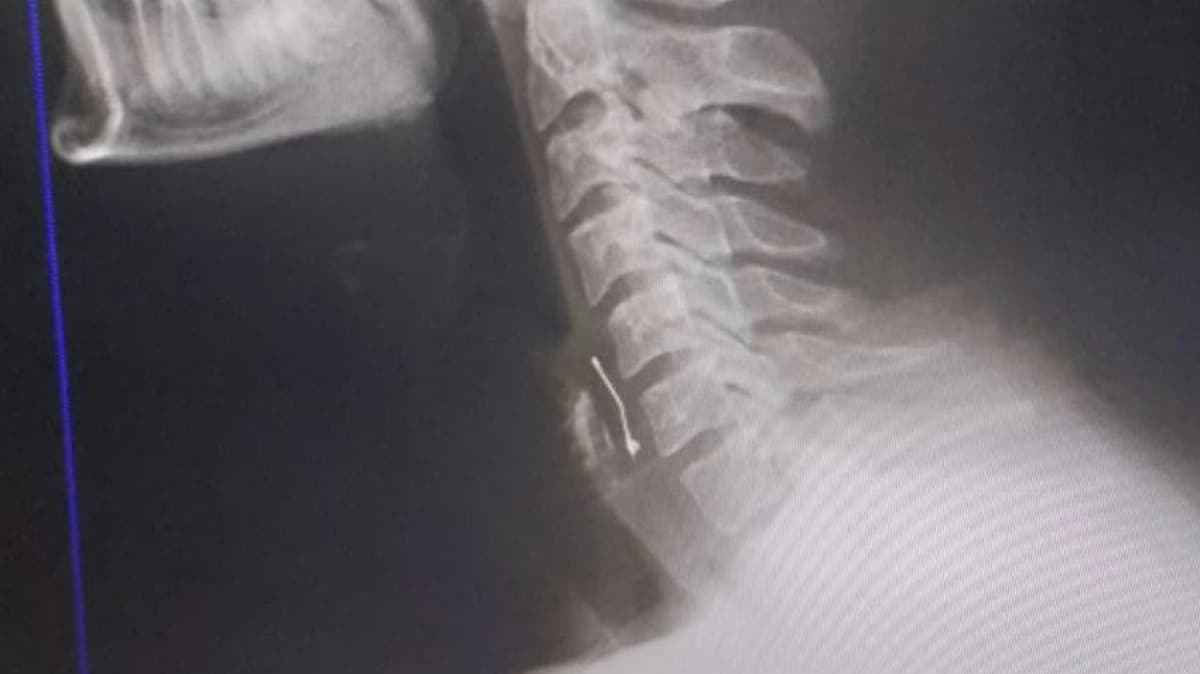

Olay, perşembe akşamı, Tekerek yolundaki pastanede meydana ageldi. Ramazan Orçan, arkadaşının doğum gününü kutlamak için pastaneye gitti. Garsonlar tarafından getirilen doğum günü pastasından yiyen Orçan, iddiaya göre, boğazında acı hisseti. Kahramanmaraş Sütçü İmam Üniversitesi Sağlık Uygulama ve Araştırma Hastanesi'ne giden Orçan'ın boğazında, çekilen röntgene bakılarak, iğne olduğu tespit edildi. Hemen ameliyata alınan Orçan'ın boğazındaki iğne çıkarıldı.

"Arkadaşımızın doğum günüydü. Pasta garsonlar tarafından getirilip ikram edildi. Pastayı yerken boğazımda bir şey durduğunu hissettim. İlk önce çikolata parçası zannettim, yutkunmaya çalıştım. Biraz yutkundum, akabinde su içtim ama orada takılı kaldı, aşağı inmedi. Daha sonra beni öksürük tuttu ve nefes alamamaya başladım. Apar topar fakültenin acil servisine geldik. Acil serviste yapılan işlemler sonrasında çekilen filmlerde boğazımda toplu iğne olduğu tespit edildi. Birkaç defa endoskopi ile almaya çalıştılar ama alamayınca ameliyat geçirdim. Ameliyatla toplu iğne bulunduğu yerden çıkarıldı. Herhangi bir şey yiyip içemiyorum, serumla besleniyorum. Süreç tamamlandıktan sonra firmayla ilgili suç duyurusunda bulunacağım."